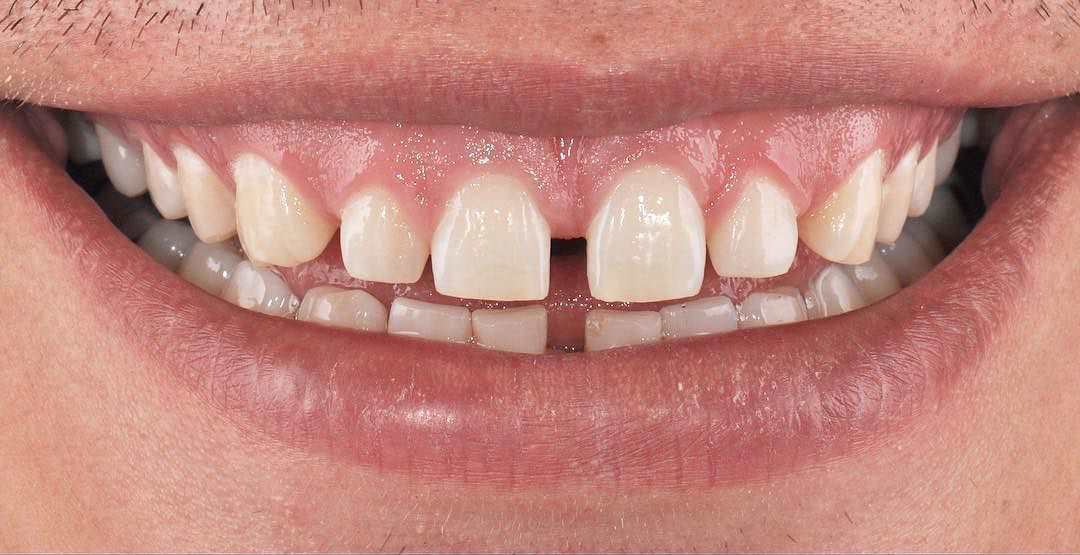

Gülüş Tasarımı

Ağız bakımı denilince akla diş ağrısı, ağız kokusu ve diş kayıpları gibi problemlerin çözümü gelse de günümüzde diş ve diş...

Devamını Oku